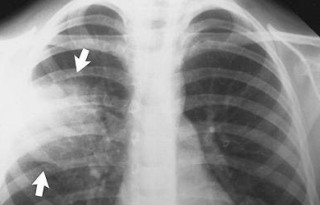

Հանրապետությունում վերջին օրերի ընթացքում սուր շնչառական խնդիրներով հոսպիտալացվել է 24 հղի կին, որոնցից 5-ի մոտ ախտորոշվել է թոքաբորբ: Այս մասին այսօր՝ դեկտեմբերի 5-ին, կառավարությունում տեղի ունեցած խորհրդակցության ժամանակ հայ...